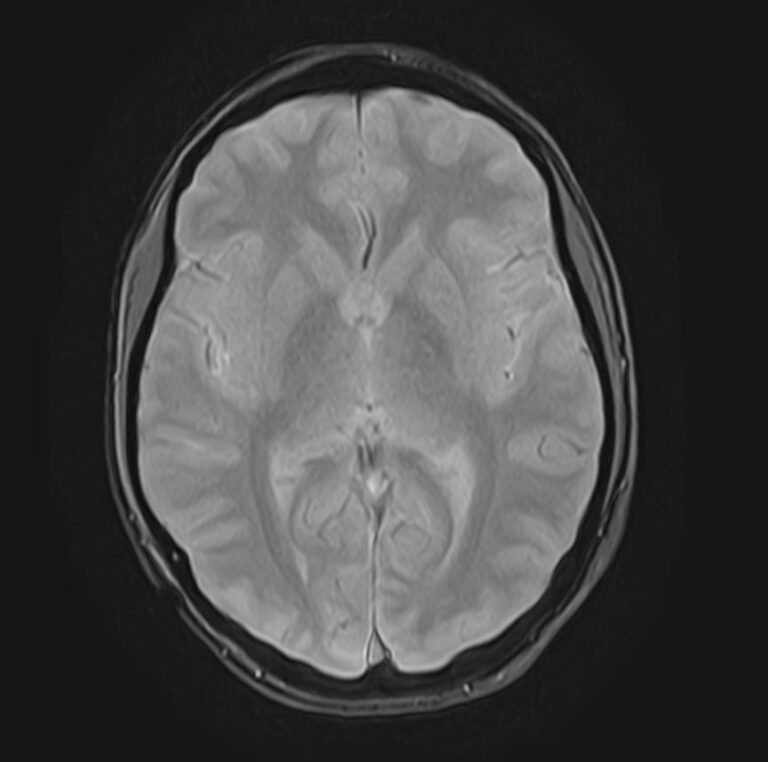

В клинике «Доступная медицина» можно пройти комплексное обследование, включающее в себя несколько протоколов сканирования близко расположенных друг от друга анатомических областей – шейного отдела позвоночника и головного мозга. Метод комплексного обследования оценивает состояние всех структур головного мозга и шейного отдела позвоночника. При этом дополнительные протоколы обследования позволяют визуализировать крупные сосуды шеи и сосудистую сеть головного мозга.

Сканирование проводится на современном высокопольном магнитно-резонансном томографе закрытого типа TOSHIBA VANTAGE TITAN 1,5 Тесла. Магнитно-резонансный томограф производит послойное сканирование исследуемой зоны в разных плоскостях, затем при помощи компьютерных программ преобразует полученные данные в трехмерные изображения. При этом кровеносная система реконструируется как вместе с окружающими тканями, так и отдельно без них.

Что показывает МРТ головного мозга + МРТ шейного отдела позвоночника + МР-ангиография шеи и головного мозга

В рамках проведения данного комплексного исследования можно выявить:

• очаги ишемического и геморрагического инсульта, область поражения, признаки отека головного мозга, стадию развития заболевания;

• доброкачественные и злокачественные новообразования, их точную локализацию, стадию развития процесса, проводить динамическое наблюдение за опухолевым процессом на фоне лечения;

• признаки демиелинизирующих заболеваний (рассеянный склероз), выявить очаги поражения миелиновой оболочки нервных волокон, определить стадию заболевания;

• характерные признаки дегенеративных заболеваний головного мозга (болезнь Альцгеймера, старческая деменция, болезнь Паркинсона), определить изменения коры головного мозга и подкорковых структур;

• поражение структур головного мозга на фоне травм, гематомы головного мозга;

• изменения, характерные для психических расстройств различного генеза (эндогенных и экзогенных), после вирусных инфекций, черепно-мозговых травм, отравлений токсическими веществами, на фоне наследственных заболеваний;

• участки сужения, извитость, образование петель и перегибов сосудов;

• нарушения оттока крови за счет тромбообразования в венозном русле;

• ангиомы, сосудистые мальформации;

• остеохондроз, спондилоартроз, спондилез, межпозвонковые грыжи, унковертебральный артроз, сколиоз, усиленный или выпрямленный лордоз как нарушение статической функции позвоночника, травмы, аномалии позвоночника.